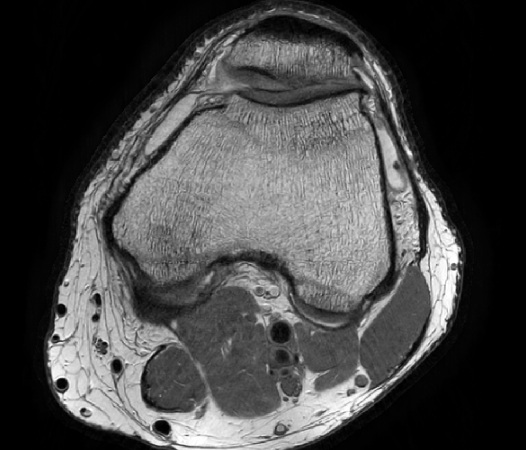

In the example below, only one fifth of the required MR radiofrequency signals is recorded. This results in a five times faster acquisition, with a subsampled k-space (top left) and inherent image artifacts after standard reconstruction (top right).

Knee with artifacts

The Compressed SENSE reconstruction then uses iterative, knowledge-based algorithms to fill in the empty lines in k-space (bottom left). This removes the artifacts while keeping the final image fully consistent with the acquired data (bottom right).